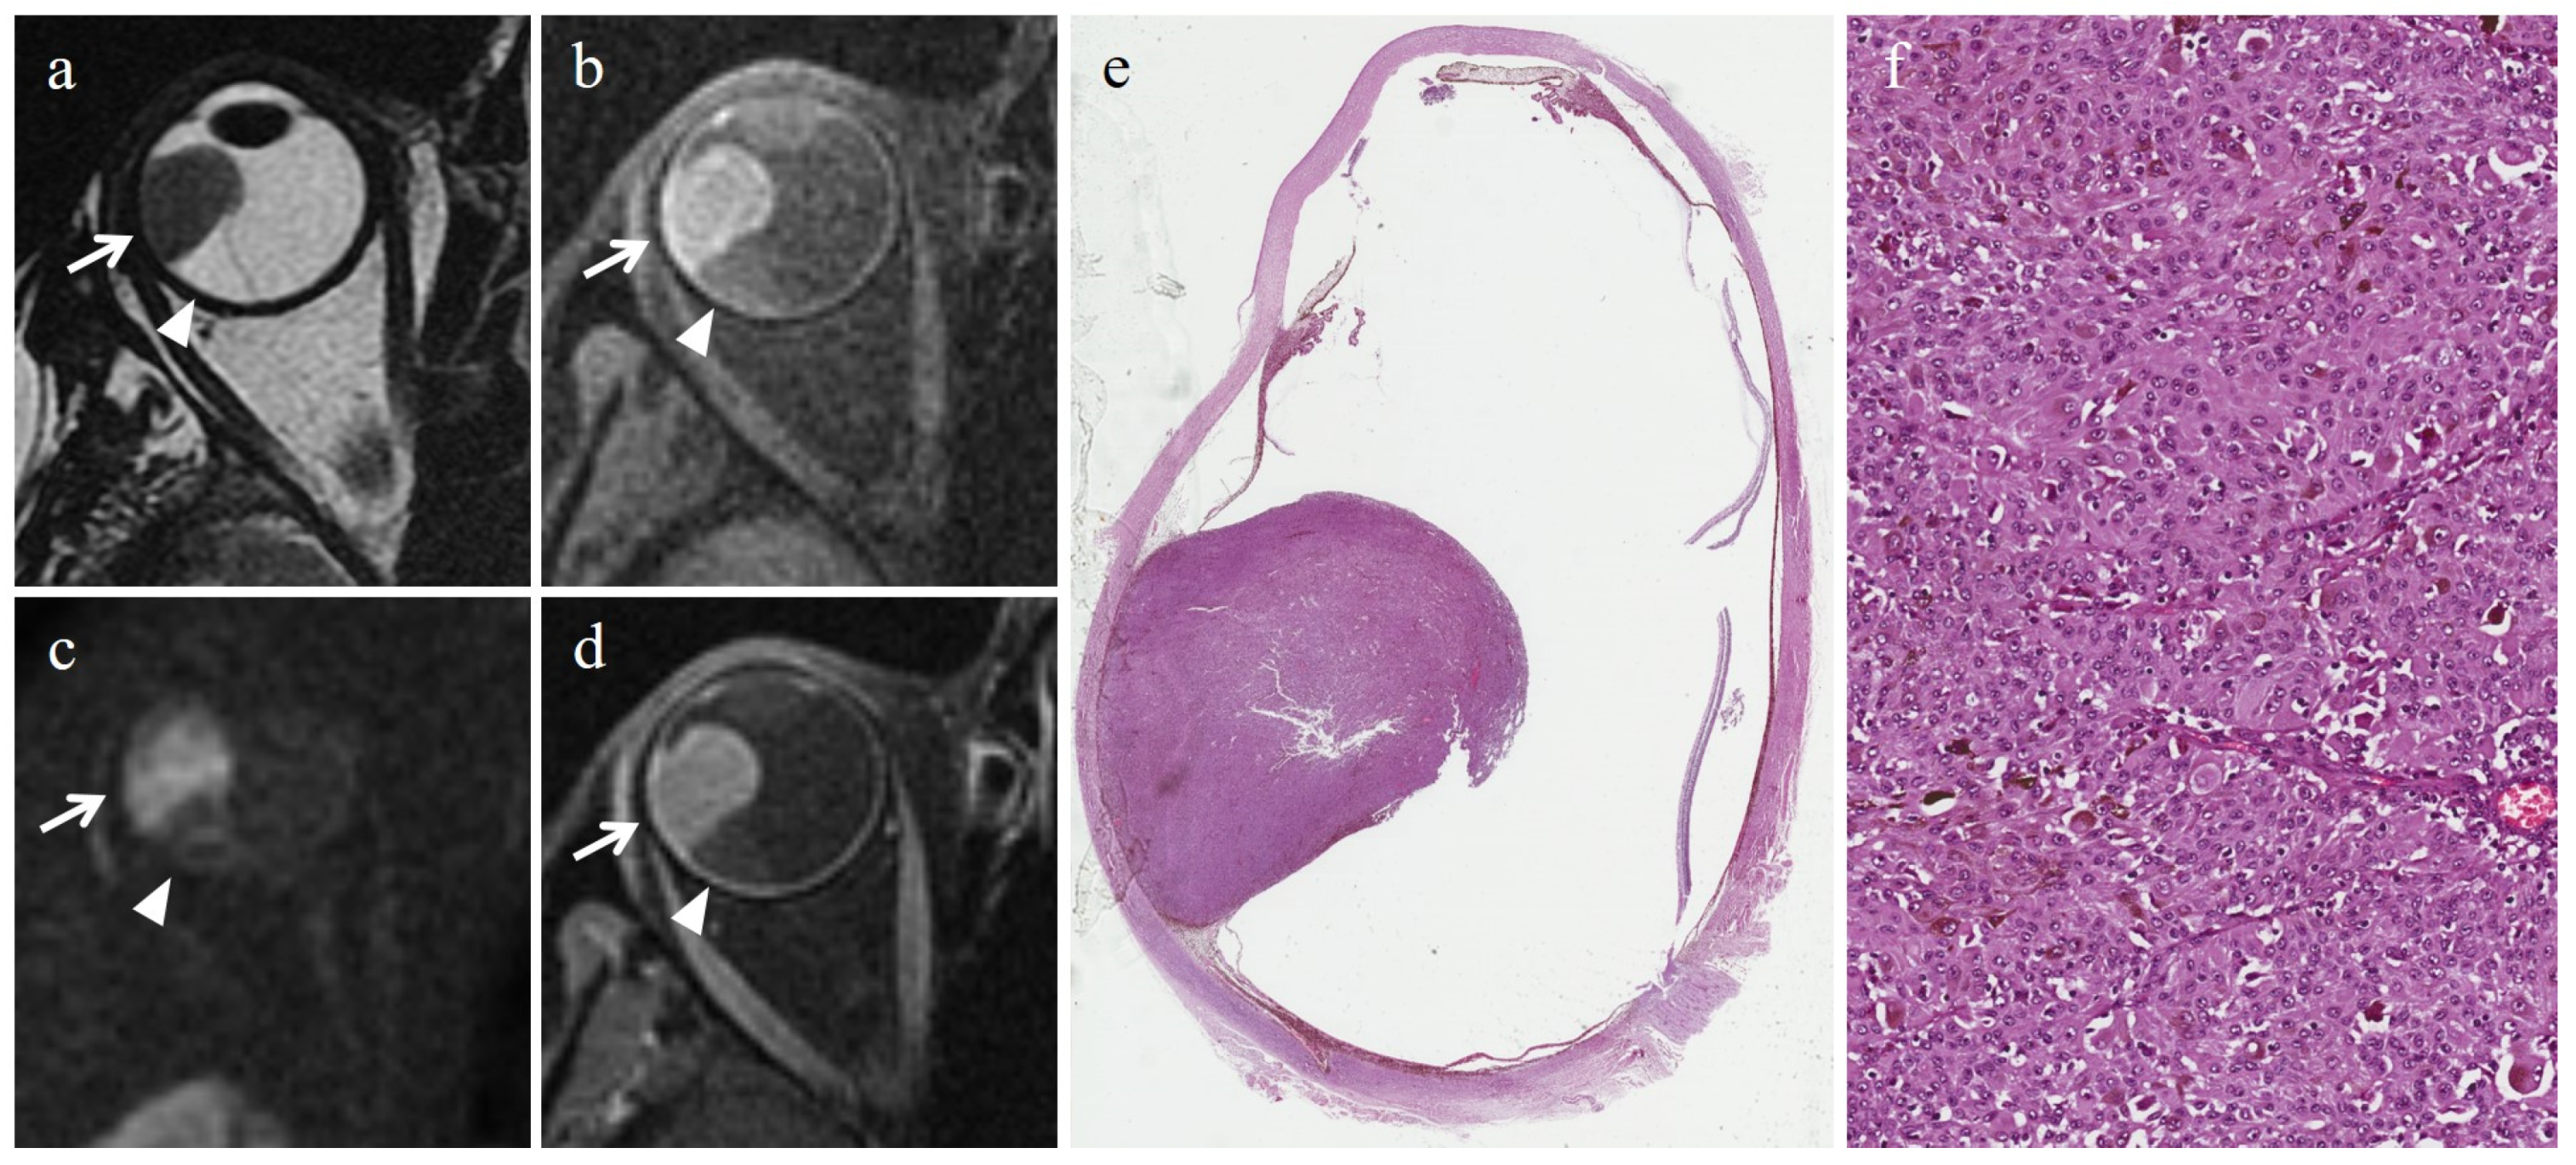

- Foti, P.V.; Inì, C.; Broggi, G.; Farina, R.; Palmucci, S.; Spatola, C.; Liardo, R.L.E.; Milazzotto, R.; Raffaele, L.; Salamone, V.; et al. Histopathologic and MR Imaging Appearance of Spontaneous and Radiation-Induced Necrosis in Uveal Melanomas: Initial Results. Cancers 2022, 14, 215. [Google Scholar] [CrossRef]